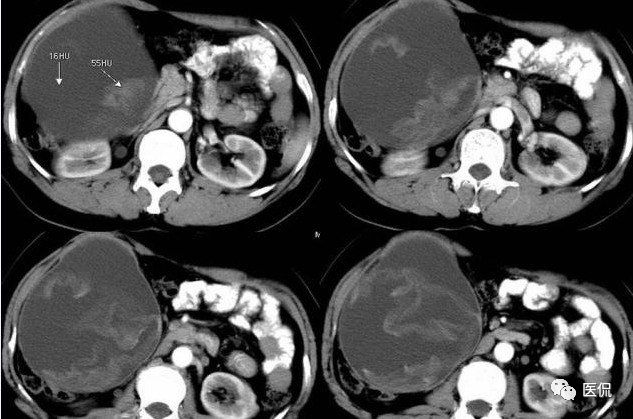

腹腔内残留的纱布在人体内引起渗出或液化坏死并纤维包裹形成异物性脓肿(纱布瘤)。纱布瘤的影像特点:圆形或卵圆形肿块,较大,有完整包膜,薄壁,较少的情况下为厚壁,边界较完整,增强后薄膜可以持续强化。不同时期的纱布瘤可以有不同表现:早期(10个月或半年内)多表现为蜂窝状;2~5年内一般表现为囊性飘带状;10~20年之后则为实性软组织密度,包膜钙化呈钙化网状结构。手术过程中残留在人体内的医用纱布所形成的肿瘤样病变。

手术所见:腹腔内无腹水,肿块位于右上腹,约15x10x8cm大小 ,周围网膜包裹粘连,向胆囊三角处延续,呈囊性,与周围结构无明显浸润,仔细分离粘连,逐步游离暴露肿块,见肿块与右肾及结肠、十二指肠无明显关系,初步确定为肿大的胆囊,继续向肝门部游离,见肿块与胃窦粘连,因分离困难,决定切开肿块。穿刺肿块有黄色脓液抽出,考虑胆囊脓肿,切开囊壁,吸出大量黄色混浊脓液约1200ml,探查囊腔,见粘膜层为胆囊粘膜,腔内有一异物残留,经证实为医用盐水纱布,取出纱布约15x15cm大小,封存。继续游离胆囊至完整切除,检查囊壁无明显占位病变。

病理诊断:胆囊异物残留,胆囊化脓性炎、胆囊脓肿。

腹腔内遗留纱布团的影像学表现,以B超较具特征性,其主要表现为:腹腔或盆腔内特殊率减的黑色包块,后方伴有扇形衰减的声影,上窄下宽,好似一“黑色大布”,早期包块内含有不规则光团或光点,随时间延长有缩小或消失,为纱布团内气体。CT的优势在于早期常表现为软组织密度的肿块,其内可见多少不等的气泡,随时间的延长气泡逐渐被吸收减少至消失,增强扫描可见包膜不同程度强化而内容物无强化。熟悉其影像学表现,可在术前作出明确诊断。